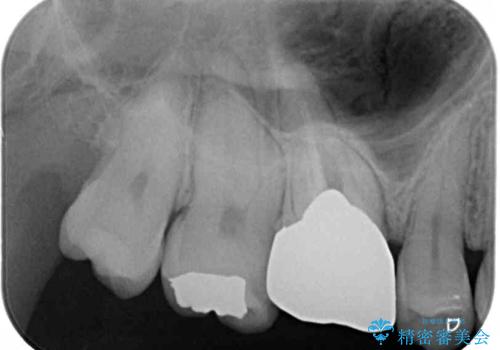

- 奥歯にものが挟まって痛みがあるとのことで来院された患者様です。

目視でも分かるくらいの欠損があり、歯の内部にむし歯が進行している状態でした。

上顎奥歯で目立たないことから、ゴールドインレー(PGAインレー)による修復治療をおこなうこととしました。